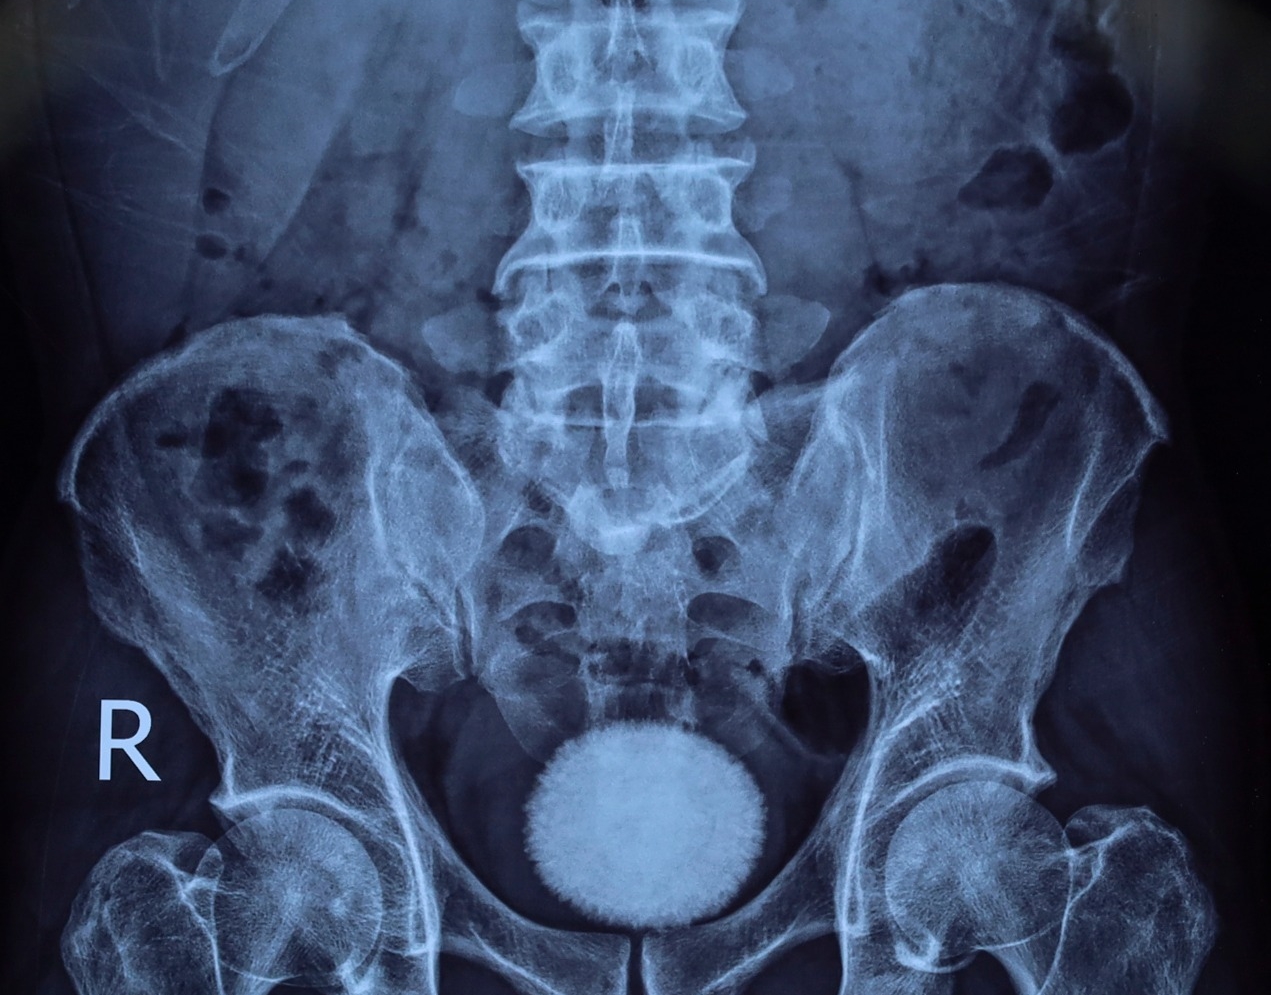

Trước đó, bệnh nhân đến khám trong tình trạng tiểu buốt, tiểu khó kéo dài, kèm đau vùng hạ vị. Qua thăm khám lâm sàng, siêu âm và chụp X-quang, các bác sĩ phát hiện trong bàng quang có viên sỏi kích thước khoảng 60×40 mm.

Nhận định đây là viên sỏi lớn, nguy cơ gây tắc nghẽn và nhiễm trùng đường tiết niệu, ê kíp bác sĩ đã chỉ định phẫu thuật mở lấy sỏi bàng quang.

Trong quá trình phẫu thuật, các bác sĩ rạch da đường giữa trên xương mu, tiếp cận bàng quang và lấy ra một viên sỏi lớn, kích thước tương đương quả trứng ngỗng. Sau khi lấy sỏi, bàng quang được bơm rửa sạch và khâu phục hồi theo đúng quy trình chuyên môn. Ca mổ diễn ra thuận lợi. Hiện bệnh nhân tỉnh táo, sức khỏe ổn định và đang được theo dõi, chăm sóc hậu phẫu.